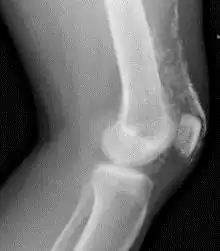

Magnetic resonance imaging may be useful to guide muscle biopsy and to investigate involvement of internal organs;[21] X-ray may be used to investigate joint involvement and calcifications.[22]